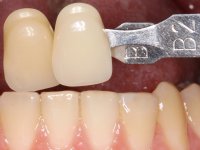

O paciente foi observado conjuntamente e a dúvida que surgiu de imediato foi se seria possível com a regeneração óssea a efectuar poder ser reabilitada naturalmente a zona das papilas interdentárias. Nesse sentido foi feito um enceramento de diagnóstico que contemplaria as duas hipóteses, utilizando ou não a cerâmica gengival. A confecção desse enceramento foi fundamental para expor ao paciente a dificuldade da reabilitação. O wax-up deu origem a um mock-up que foi aprovado pelo paciente e que simultaneamente serviu de guia imagiológica. O caso foi planificado cirurgicamente e realizada uma guia cirúrgica com que foram colocados os implantes. Após 10 semanas foi feita a 1ª impressão para confecção da ponte provisória. Foram criados os primeiros perfis de emergência na gengiva artificial e foi digitalizado o modelo. Por processo de CAD-CAM foi confeccionada uma ponte provisória aparafusada baseada no enceramento de diagnóstico. A ponte trabalhou durante 8 semanas os tecidos moles que foram fielmente copiados numa impressão com técnica de moldeira aberta. Os transferes foram individualizados com resina composta para copiarem fielmente os perfis de emergência criados pela ponte provisória. Confeccionado o modelo de trabalho definitivo, foi realizada uma infra-estrutura em zircónio seguindo a orientação do enceramento de diagnóstico. O assentamento da infra-estrutura foi testado em boca e simultaneamente foi novamente impressionados os tecidos moles com um silicone fluido. Nessa consulta foi feito o levantamento da cor. Os dentes 13 e 23 apresentavam uma saturação anormalmente forte que resolvemos não valorizar, optando por privilegiar a relação com o sector antero-inferior. Foi realizada uma nova gengiva artificial com a impressão que acompanhou a impressão de arrasto com a infra-estrutura. Após a colocação da cerâmica na infra-estrutura foram coladas as meso-estruturas. O trabalho final foi aparafusado lentamente permitindo a adaptação dos tecidos moles.